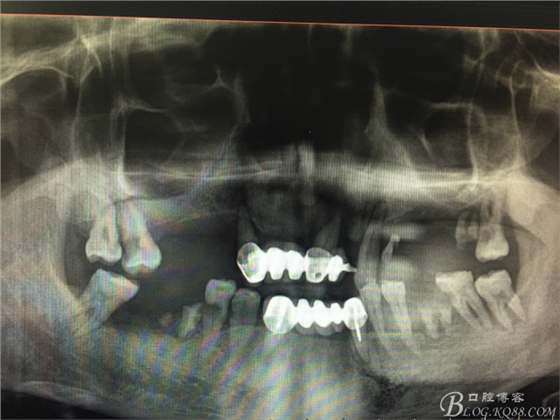

患者37歲 男 全口牙周病 手術(shù)一次完成 全程3小時全口種植修復(fù)全口種植修復(fù)全口種植修復(fù)全口種植修復(fù)全口種植修復(fù)全口種植修復(fù)全口種植修復(fù)全口種植修復(fù)全口種植修復(fù)全口種植修復(fù)全口種植修復(fù)全口種植修復(fù)全口種植修復(fù)全口種植修復(fù)全口種植修復(fù)